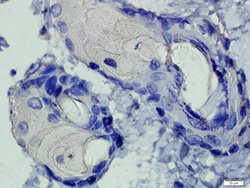

- Submitted by

- antibodies-online (provider)

- Main image

- Experimental details

- IHC